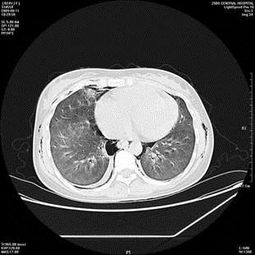

百草枯可怕在于它没有解药,并没有后悔的余地, 到头来几乎是 想死的时候死不了想活的时候活不成 。.肺是主要靶器官,百草枯对肺的伤害Zui大, 大量口...

百草枯可怕在于它没有解药并没有后悔的余地,到头来几乎是 想死的时候死不了想活的时候活不成 。.肺是主要靶器官,百草枯对肺的伤害Zui大,大量口服者,24小时内出现肺水肿,肺出血,常在数天内因急性呼吸窘迫综合征而死亡;非大量口服摄入者呈亚急性经过一般在1周左右出现胸闷、憋气,2-3周呼吸困难达到高峰,再说说引起肺纤....